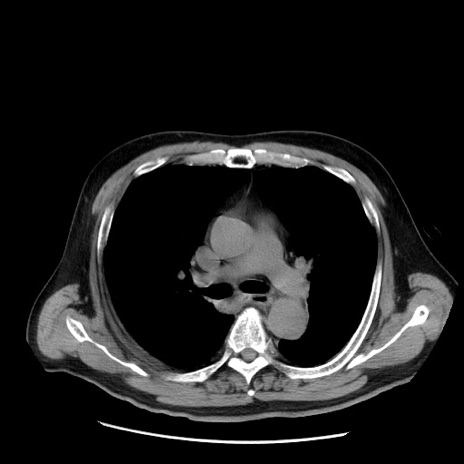

症例20(横断像)

【症例】 60歳代男性

【主訴】 腹部膨満、嘔吐

【現病歴】5日前頃より倦怠感を認め食事量減少し4日前の朝嘔吐、食事摂取困難となった。 3日前近医受診し点滴施行され整腸剤などを処方された。 当日他院を受診し、腹部膨満著明、炎症反応の上昇(CRP10.8、WBC11200)あり、紹介受診となる。

【身体所見】 意識JCS1 受け答えがはっきりしないBP 111/57mHg、 P 67bpm、、BT35.2°C、SpO2 97%(RA)、 腹部:膨隆、打診で鼓音あり、全体的に圧痛有り、腸蠕動音(-)、反跳痛ははっきりせず。

【データ】WBC 11400、CRP 14.20